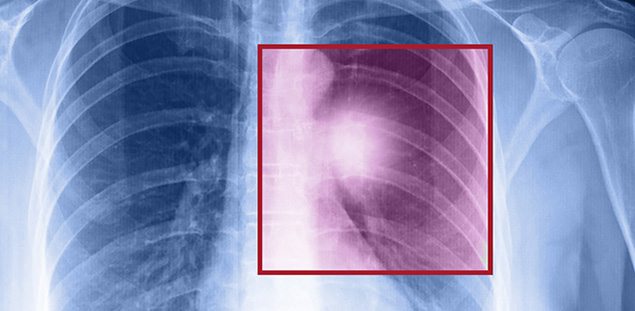

Akciğer kanseri yapısal olarak normal akciğer dokusundan olan hücrelerin ihtiyaç ve kontrol dışı çoğalarak akciğer içinde bir kitle (tümör) oluşturmasıyla başlıyor. Burada oluşan kitle öncelikle bulunduğu ortamda büyüyor, daha ileri aşamalarda ise çevre dokulara veya dolaşım yoluyla uzak organlara (karaciğer, kemik, beyin, vb) yayılarak hasara yol açıyor.

Akciğer kanserlerinde tedavinin belirlenmesinde en önemli faktörler kanserin tipi ve evresi. Uygun hastalarda cerrahi yöntemlerle kanserin bulunduğu akciğer veya akciğer bölümü çıkartılabiliyor. Cerrahi için elverişli olmadığı düşünülen hastalarda ise kemoterapi uygulanabilmekte.